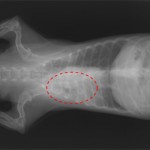

체표림프절이 비대되었고 복부에 내출혈이 있었기 때문에 내원. 5일후에 좌측 슬와(膝窩)림프절을 적출하였으며 병리검사에서 악성림프종으로 진단되었다.

7월에 비장의 비대가 확인되었기 때문에 위의 치료와 함께 항암제도 몇 차레 투여하였다.